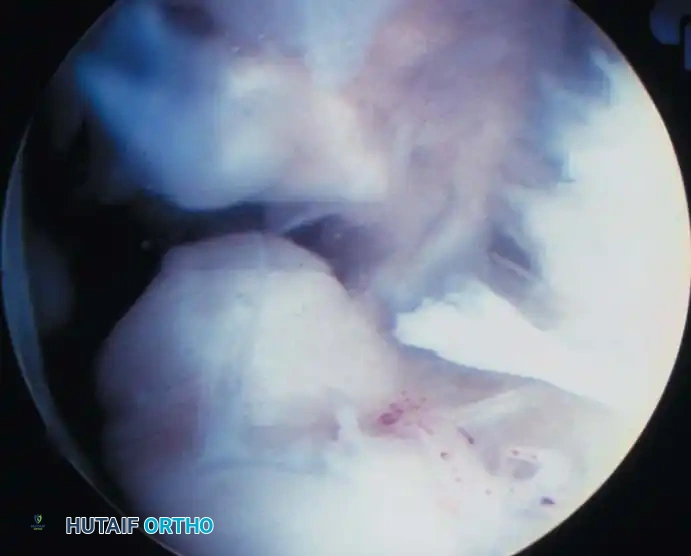

Arthroscopic view of the anterolateral gutter demonstrating synovial hypertrophy and soft-tissue impingement.

Arthroscopic visualization of an osteochondral defect (OCD) on the medial talar dome.

Arthroscopic view of the posterior gutter, a common hiding place for intra-articular loose bodies.

Further visualization of the posterior compartment structures, including the transverse ligament.